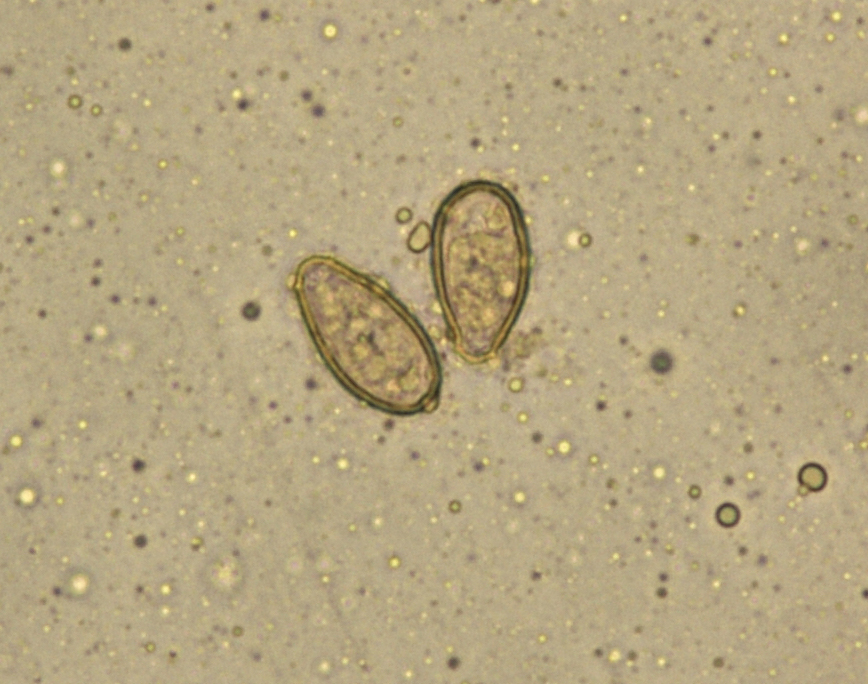

Гельминты у хищных птиц - фото презентация